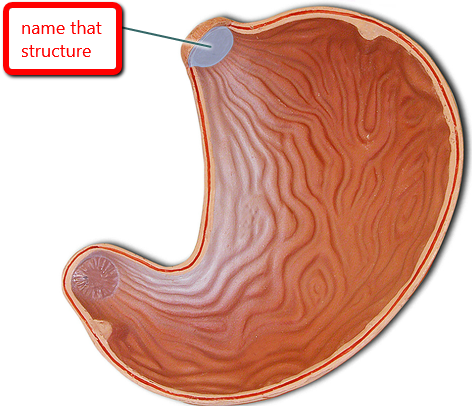

Gastroesophageal sphincter

Rugae (of stomach)

Stomach

Fundus (of stomach)

Body (of stomach)

Pylorus (of stomach)

Cardia (of stomach)